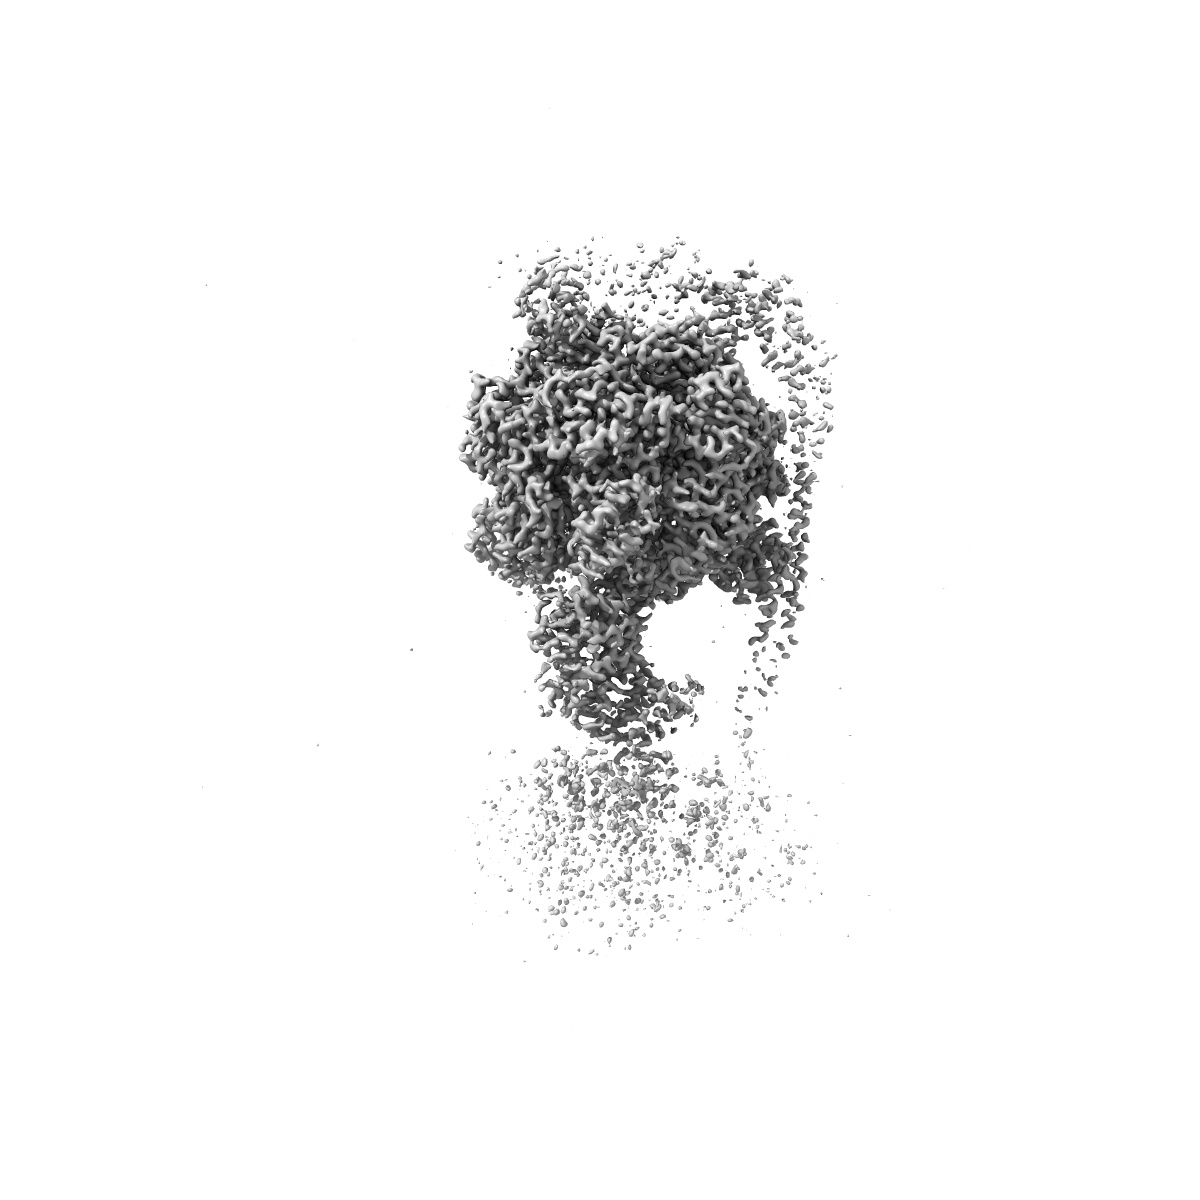

Cryo-EM structure of Mycobacterium tuberculosis ATP synthase F1 in complex with TBAJ-587

Sample Organism: Mycobacterium tuberculosis

Sample: Mycobacterium tuberculosis ATP synthase

Deposition Authors: Zhang Y, Lai Y, Liu F , Rao Z, Gong H

Inhibition of M. tuberculosis and human ATP synthase by BDQ and TBAJ-587.

Zhang Y, Lai Y, Zhou S, Ran T , Zhang Y, Zhao Z, Feng Z, Yu L, Xu J, Shi K, Wang J, Pang Y, Li L, Chen H, Guddat LW , Gao Y , Liu F , Rao Z, Gong H

(2024) Nature , 631 , 409 - 414

PUBMED: 38961288

DOI: doi:10.1038/s41586-024-07605-8